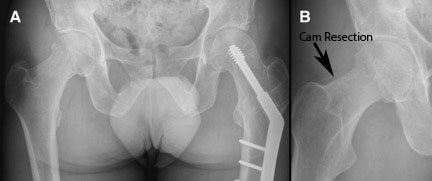

Pascual-Garrido said she considered a micro-fracture procedure as an option when she began the surgery, but decided on the DeNovo graft because of the size of the lesion and Rogers’ age. She noted that while the surgery went very well, the wear-and-tear on the joint could eventually progress to osteoarthritis and possibly require hip replacement. But the DeNovo graft doesn’t close off any subsequent options for Rogers, including alternative stem cell procedures to rebuild cartilage.

For now, the DeNovo procedure is considered experimental for hip repair, but Pascual-Garrido, who learned the technique doing knee surgeries, said there is reason for optimism.